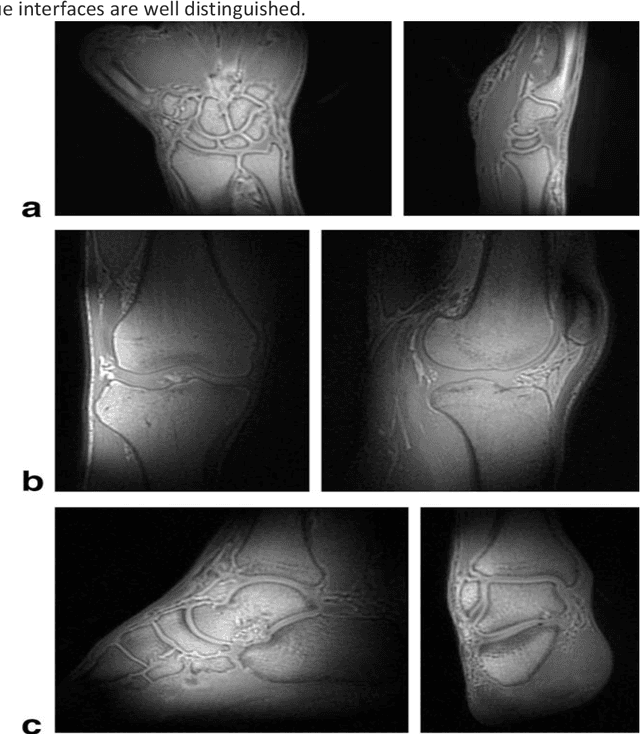

Abstract:UTE (Ultrashort Echo Time) and ZTE (Zero Echo Time) sequences have been developed to detect short T2 relaxation signals coming from regions that are unable to be detected by conventional MRI methods. Due to the high dipole-dipole interactions in solid and semi-solid tissues, the echo time generated is simply not enough to produce a signal using conventional imaging method, often leading to void signal coming from the discussed areas. By the application of these techniques, solid and semi-solid areas can be imaged which can have a profound impact in clinical imaging. High and Ultra-high field strength (UHF) provides a vital advantage in providing better sensitivity and specificity of MR imaging. When coupled with the UTE and ZTE sequences, the image can recover void signals as well as a much-improved signal quality. To further this strategy, secondary data from various research tools was obtained to further validate the research while addressing the drawbacks to this approach. It was found that UTE and ZTE sequences coupled with some techniques such as qualitative imaging and new trajectories are very crucial for accurate image depiction of the areas of the musculoskeletal system, neural system, lung imaging and dental imaging.